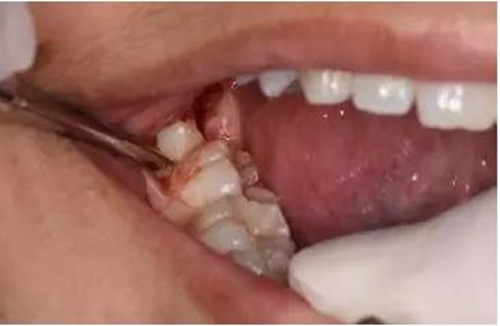

圖12. 近中、頰側(cè)兩個部位用挺使48牙冠完全脫位

圖13.清理牙槽窩、對位傷口

圖14.僅在遠(yuǎn)中縫合兩針,不宜太緊。